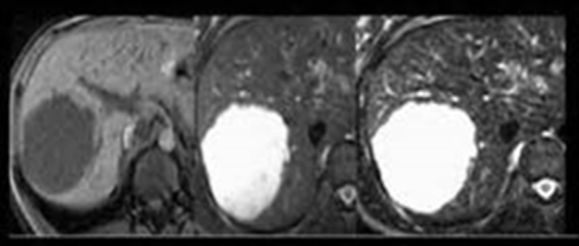

Şəkil. Hepatoblastoma

Diaqnostikası

Şübhə

• Uşaq yaşlarında qaraciyərdə törəmə tapılarsa ilk növbədə hepatoblastomadan şübhələnmək lazımdır.

• Alfa-fetoprotein əksər hallarda yüksəlir.

Dəqiqləşdirmə

• Görüntüləmə əlamətlərinə görə qaraciyərin digər şişlərindən ciddi fərqlənmir- hipoexoik, hipodens, hipervaskulyar, T1-də hipointens, T2-də hiperintens, heterogen.

• Dəqiq diaqnozu patohistoloji müayinədə qoyulur.